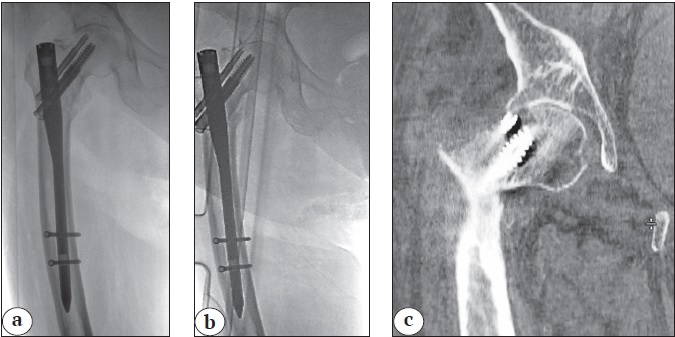

The wedge effect, which develops during nail insertion and leads to the lateralization of the diaphyseal fragment and relative lengthening of the femoral neck, was noted in 10 patients (9.3%) (Figure 1). A pathological medial gap between fragments exceeding 10 mm was observed in 7 (6.5%) patients (Figure 2), and negative medial support was noted in 3 (2.7%) patients (see Figure 1). Significant rotational deformity of the femoral neck with increased anteversion of the head was detected in 3 (2.7%) patients.

Figure 2. Reverse wedge effect leading to the formation of a pathological calcar gap: a — initial X-ray; b — X-rays after osteosynthesis; с — valgus displacement of the proximal fragment, reverse wedge effect

Pathological calcar gap

Y. Zhang et al. described the reverse wedge effect, which may take place in case of intramedullary osteosynthesis for type 31A1 and 31A2 fractures. During implant insertion, impingement occurs between the nail (or drill) and the proximal wall of the neck fragment, leading to internal rotation of the femoral neck and the formation of a gap in the medial contact area (see Figure 2). The authors report that this effect occurs in 7.97% of cases, with an average gap size of 9.2±4.6 mm [20].

Such fragment displacement can lead to incorrect implant positioning, mechanical complications, and delayed fracture healing. H. Song et al., studying this effect, concluded that the calcar gap should not exceed 4.2 mm on the AP view and 3.8 mm on the lateral view. Otherwise, the risk of losing anteromedial support increases, leading to excessive sliding of the femoral head and neck fragment. In the group of patients with the loss of medial support, the average gap on the AP view X-ray was 7.09 mm, and on the lateral X-ray, it was 5.89 mm in 46 cases. During follow-up, varus deformity greater than 10° was noted in 10 (21.7%) patients, and excessive sliding greater than 10 mm was noted in 8 (17.4%) patients [13]. In our study, a pathological calcar gap of 10 mm or more was observed postoperatively on the AP view X-ray in 7 (6.5%) patients.